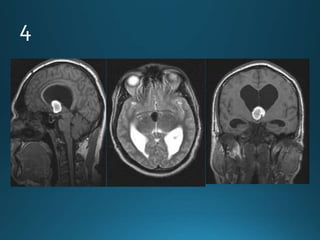

Giant cerebral aneurysms are ones that measure >25 mm in

greatest dimension.

Most commonly represent saccular cerebral aneurysms but

may also be fusiform or serpentine in morphology .They are

thought to develop via two pathways :

• internal elastic lamina de novo defect

• enlargement from a smaller aneurysm

MRI

On MRI also the patent and thrombosed aneurysm display different imaging

features:

T1

most of the patent aneurysm appears as flow void, or they may show

heterogeneous signal intensity

in thrombosed aneurysm appearance depends on the age of clot within the

lumen

T2

typically hypointense

laminated thrombus may show a hyperintense rim